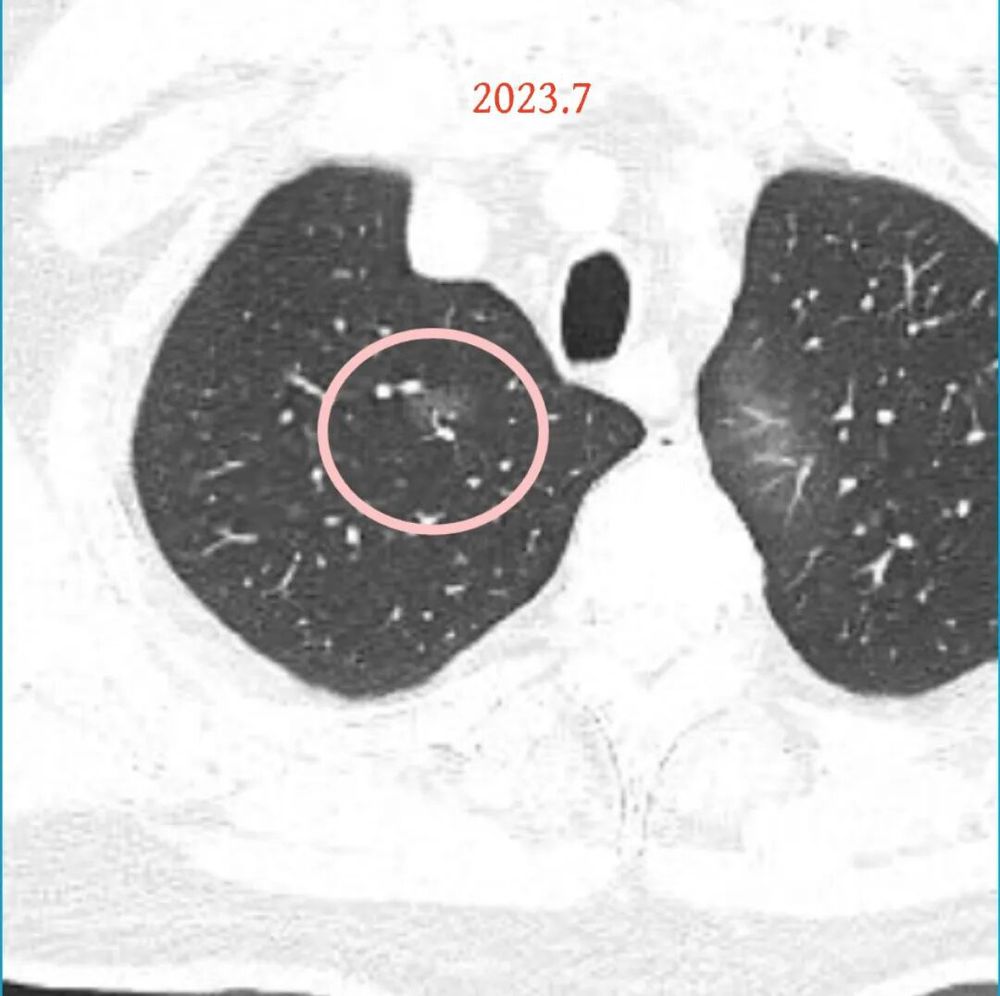

方形的是25年的,红色的主病灶,磨玻璃密度伴少许略偏高点密度,但还说不上典型混合磨玻璃病灶,考虑原位癌或微浸润性腺癌可能性大;蓝色的轮廓与边界欠清,位置靠上叶中央,无法段切或楔切;黄色的多发均淡而纯,分布在两肺。圆形粉色的是主要的两处23年时的样子,对比说不上很明显进展。鉴于若手术得切肺叶,何况两肺他处仍的结节,年纪又74了。我倾向保守点,先6-9个月复查,等进展并风险增加再来考虑怎么办的事。意见供参考!

病灶B似乎灶内有少许密度略偏高,但瘤肺边界欠清晰,总体说不上太显著的进展。

当时结友自己还觉得有点实性成分,血管感觉也有增粗。而我觉得整体密度仍是磨玻璃,轻微的变化仍不足以影响临床决策的程度。